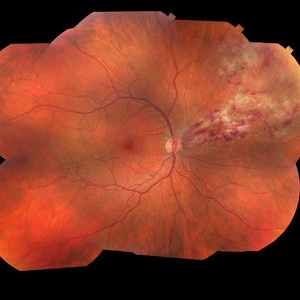

Proliferative Diabetic Retinopathy

Fluorescein angiogram series of an 30-year-old male with proliferative diabetic retinopathy affecting his right eye. The patient presented with worsening neovascularization and scar tissue contracting in macula in the right eye. He experienced a decline in vision secondary to macula ischemia. Patient was seeing 20/400 and with PH 20/200 in the right eye and HM in the left eye.

Photographer: Olivia Rainey

Imaging device: Heidelberg Spectralis

Condition/keywords: diabetes, FA early phase, FA late phase, FA mid phase, fluorescein leakage, fundus autofluorescence (FAF), neovascularization (NV), proliferative diabetic retinopathy (PDR)